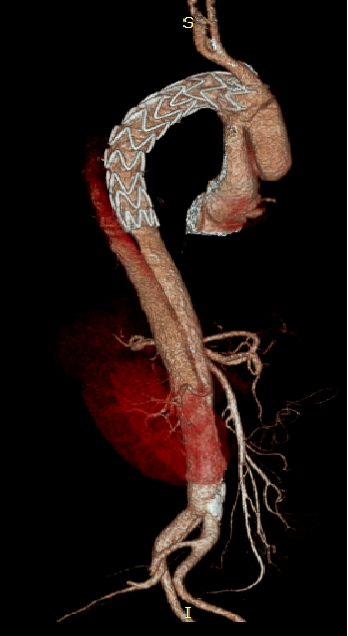

男性,44岁,慢性B型夹层。2010年12月行TEVAR术。

2013年5月发现RTAD,未处理。2015年2月死亡。

▎病例二

男,52岁,慢性夹层。2015年8月入院,4年前曾因B型层行TEVAR术,主动脉解剖变异,扭曲。行双烟囱+TEVAR术。术后第3天RTAD ,死亡。

▎病例三

男,60岁,慢性夹层。2013年12月行Debranching+TEVAR术 。2016年7月复查: RTAD ,未手术。失访。

▎病例四

男, 49岁,急性夹层 。2018年11月TEVAR。一月后复查:RTAD 。 2019年1月双开窗。2019年4月2日 复查,结果良好。